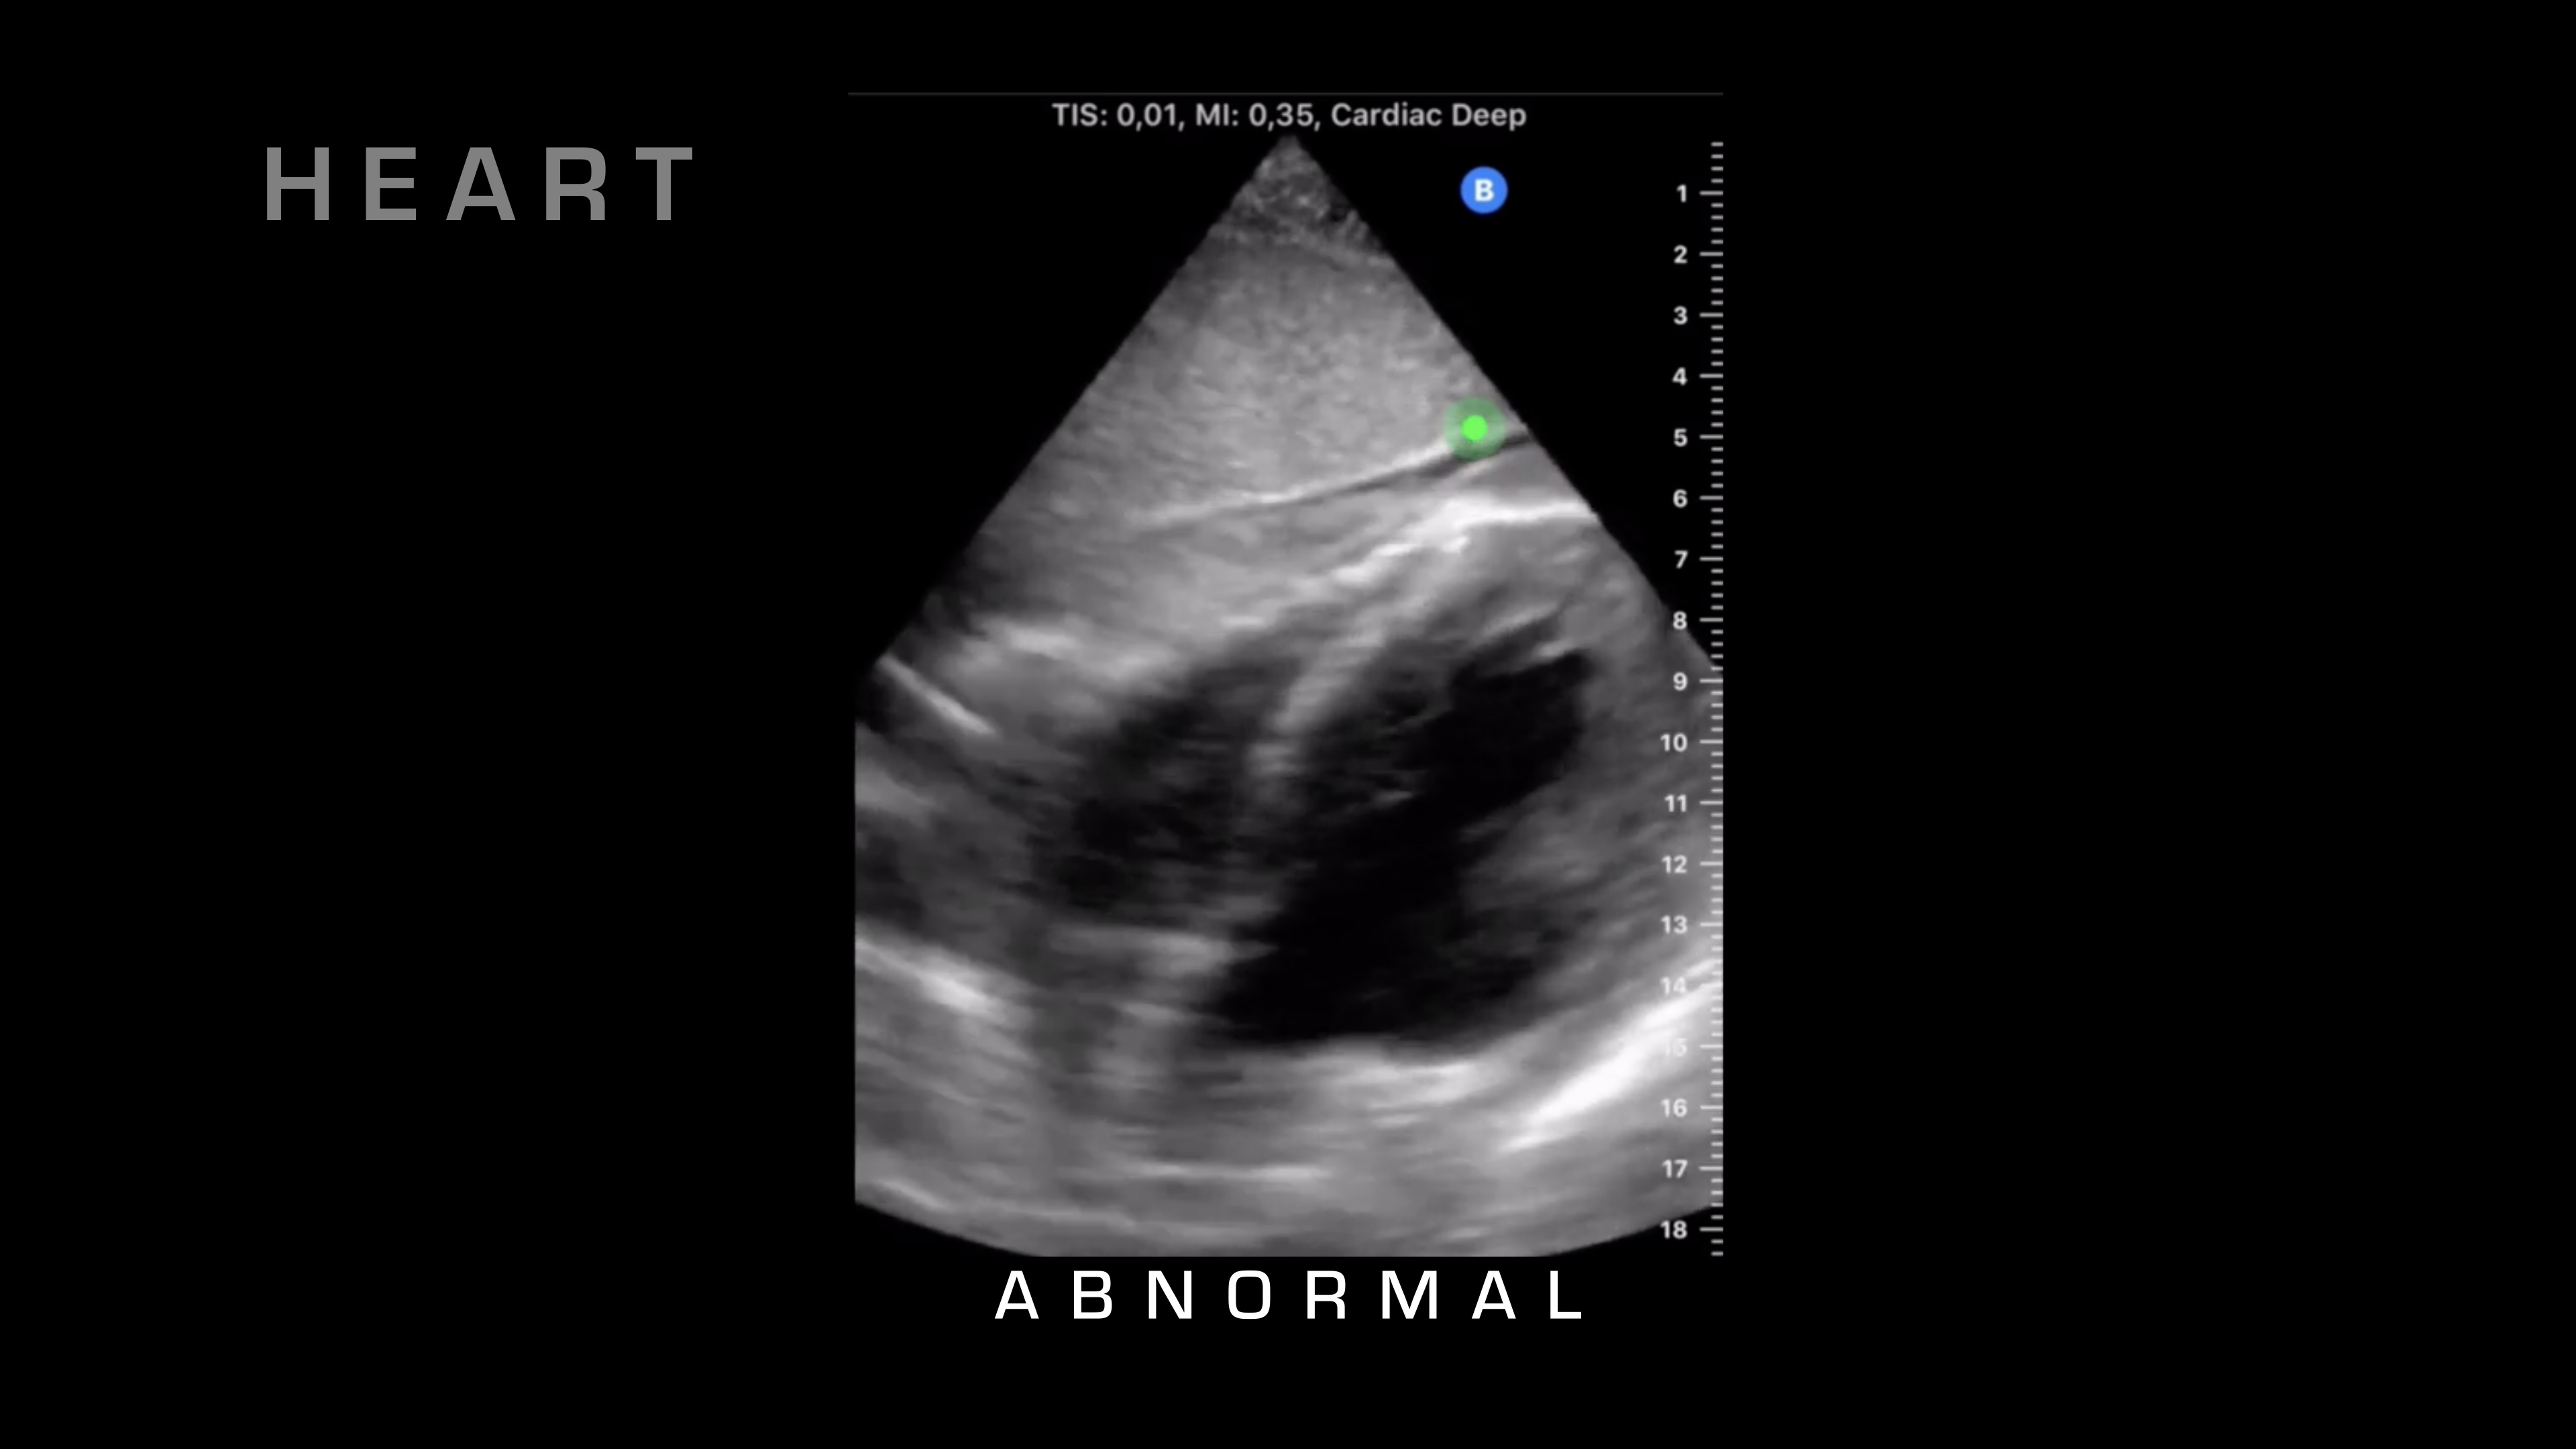

So next up on our FAST exam, what we're going to do is we're going to take a look for cardiac tamponade, and we can also get a nice view of cardiac activity. So for cardiac tamponade, what I'm looking at is the heart beating. I'm looking for that sac surrounding the heart, and then if there's fluid in between those two, typically there shouldn't be any fluid between those two, but in cardiac tamponade, fluid will go in there, blood will go into that cavity, and it'll build up and build up, then restricting the heart and reducing cardiac output.